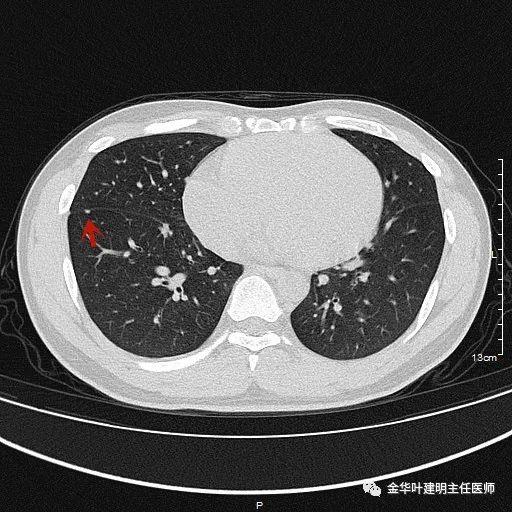

1、以下这种结节是体检发现中最常见的,它们基本上是良性的,可以年度复查:它们都是又上又实的微小结节,直径在5毫米左右或以下。实际上有许多非常焦虑的肺结节病友,他们很多人只是检查发现这种结节。我的建议是:年度复查!若实在不放心,也可半年时复查一次,以确定它不会生长。

叶建明谈结节:检查发现肺实性结节怎么办?个人版实用指南